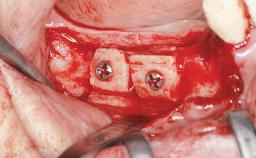

Bone Augmentation Horizontal|Sinus Floor Elevation|Staged|Vertical

Augmentation Materials Autogenous chips|Autogenous block(s)|Xenogenous|Membrane

Bone Volume Deficient vertically or deficient vertically AND horizontally